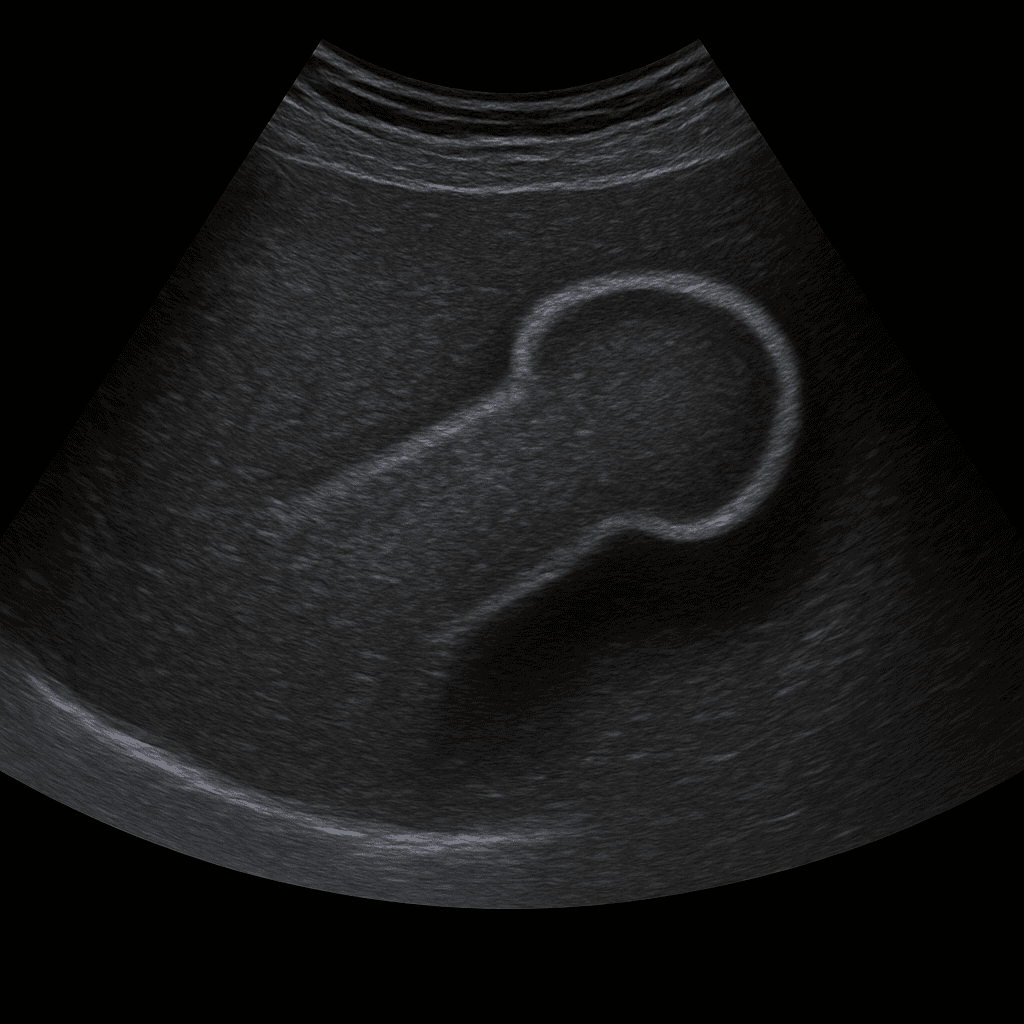

Ett ultraljud av penis används för att undersöka vävnad, blodflöde och eventuella strukturella förändringar i penisskaftet. Undersökningen utförs av specialistläkare inom radiologi och ger bilder i realtid som kan visa kärlförändringar, ärrbildning, förkalkningar eller tecken på skador. Ultraljud penis används ofta vid smärta, svullnad, kurvatur eller misstänkt kärlpåverkan.

Till skillnad från MR eller DT, som används vid mer omfattande vävnadsskador eller tumörutredning, är ultraljud en snabb, strålningsfri och effektiv metod för att bedöma kärlflöde och mjukdelar i penisskaftet. Med dopplerteknik kan läkaren analysera blodflödet i svällkropparna i realtid.

Undersökningen utförs vanligtvis när du ligger på rygg. En gel appliceras på huden och läkaren för ultraljudsproben längs penisskaftet för att bedöma vävnad och kärlflöde. Undersökningen tar cirka 10–15 minuter och är helt smärtfri. Vid behov används dopplerteknik för att studera blodcirkulationen i svällkropparna, ibland efter att ett kärlvidgande läkemedel har injicerats för att simulera erektion.